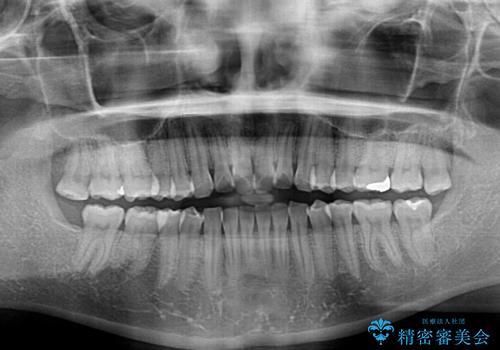

- 前歯の翼状捻転を気にして来院された患者様です。

全体的に叢生は軽度であったため、インビザラインにて矯正治療を行うこととしました。

前歯の幅の大きさも気になっていたため、IPRにより叢生を解消するとともに、歯の大きさも改善しました。